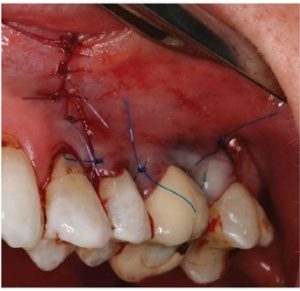

The flap was closed with Ethicon 5-0 Prolene monofilament sutures (Figure 14) and a post-operative radiograph was taken (Figure 15).

The patient was directed to use 800 mg of ibuprofen and l000 mg of acetaminophen for pain and to rinse with chlorhexidine.

Sutures were removed in seven days and the patient reappointed for reassessment. The re-evaluation radiograph taken at nine months showed substantial osseous regeneration (Figure 16) and a post-operative CBCT scan was taken after one year, showing complete bone regeneration and continuity of the buccal plate. (Figure 17).